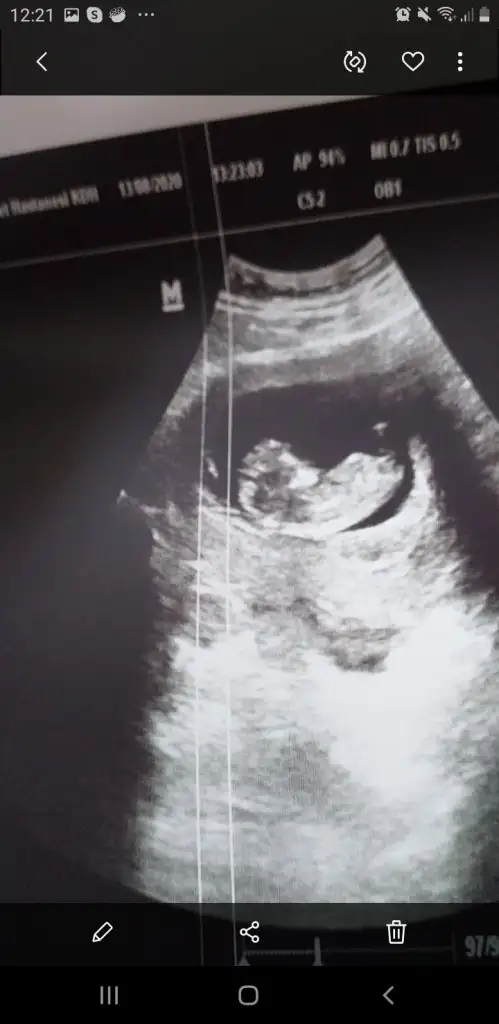

• Screenshot_20200824-122157_Gallery.webp

Screenshot_20200824-122157_Gallery.webp

18 KB · Görüntüleme: 100